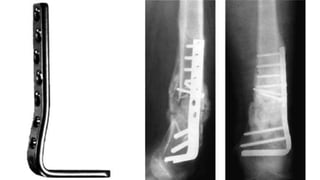

Blade plate fixation :

• Indications

Not commonly used, technically difficult

Contraindicated in type C3 fractures

• Technique

Placed 1.5 cm from articular surface